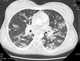

Varicella pneumonia

Chickenpox, also known as varicella, is a highly contagious disease caused by the initial infection with varicella zoster virus (VZV). The disease results in a characteristic skin rash that forms small, itchy blisters, which eventually scab over. [Source: Wikipedia ]